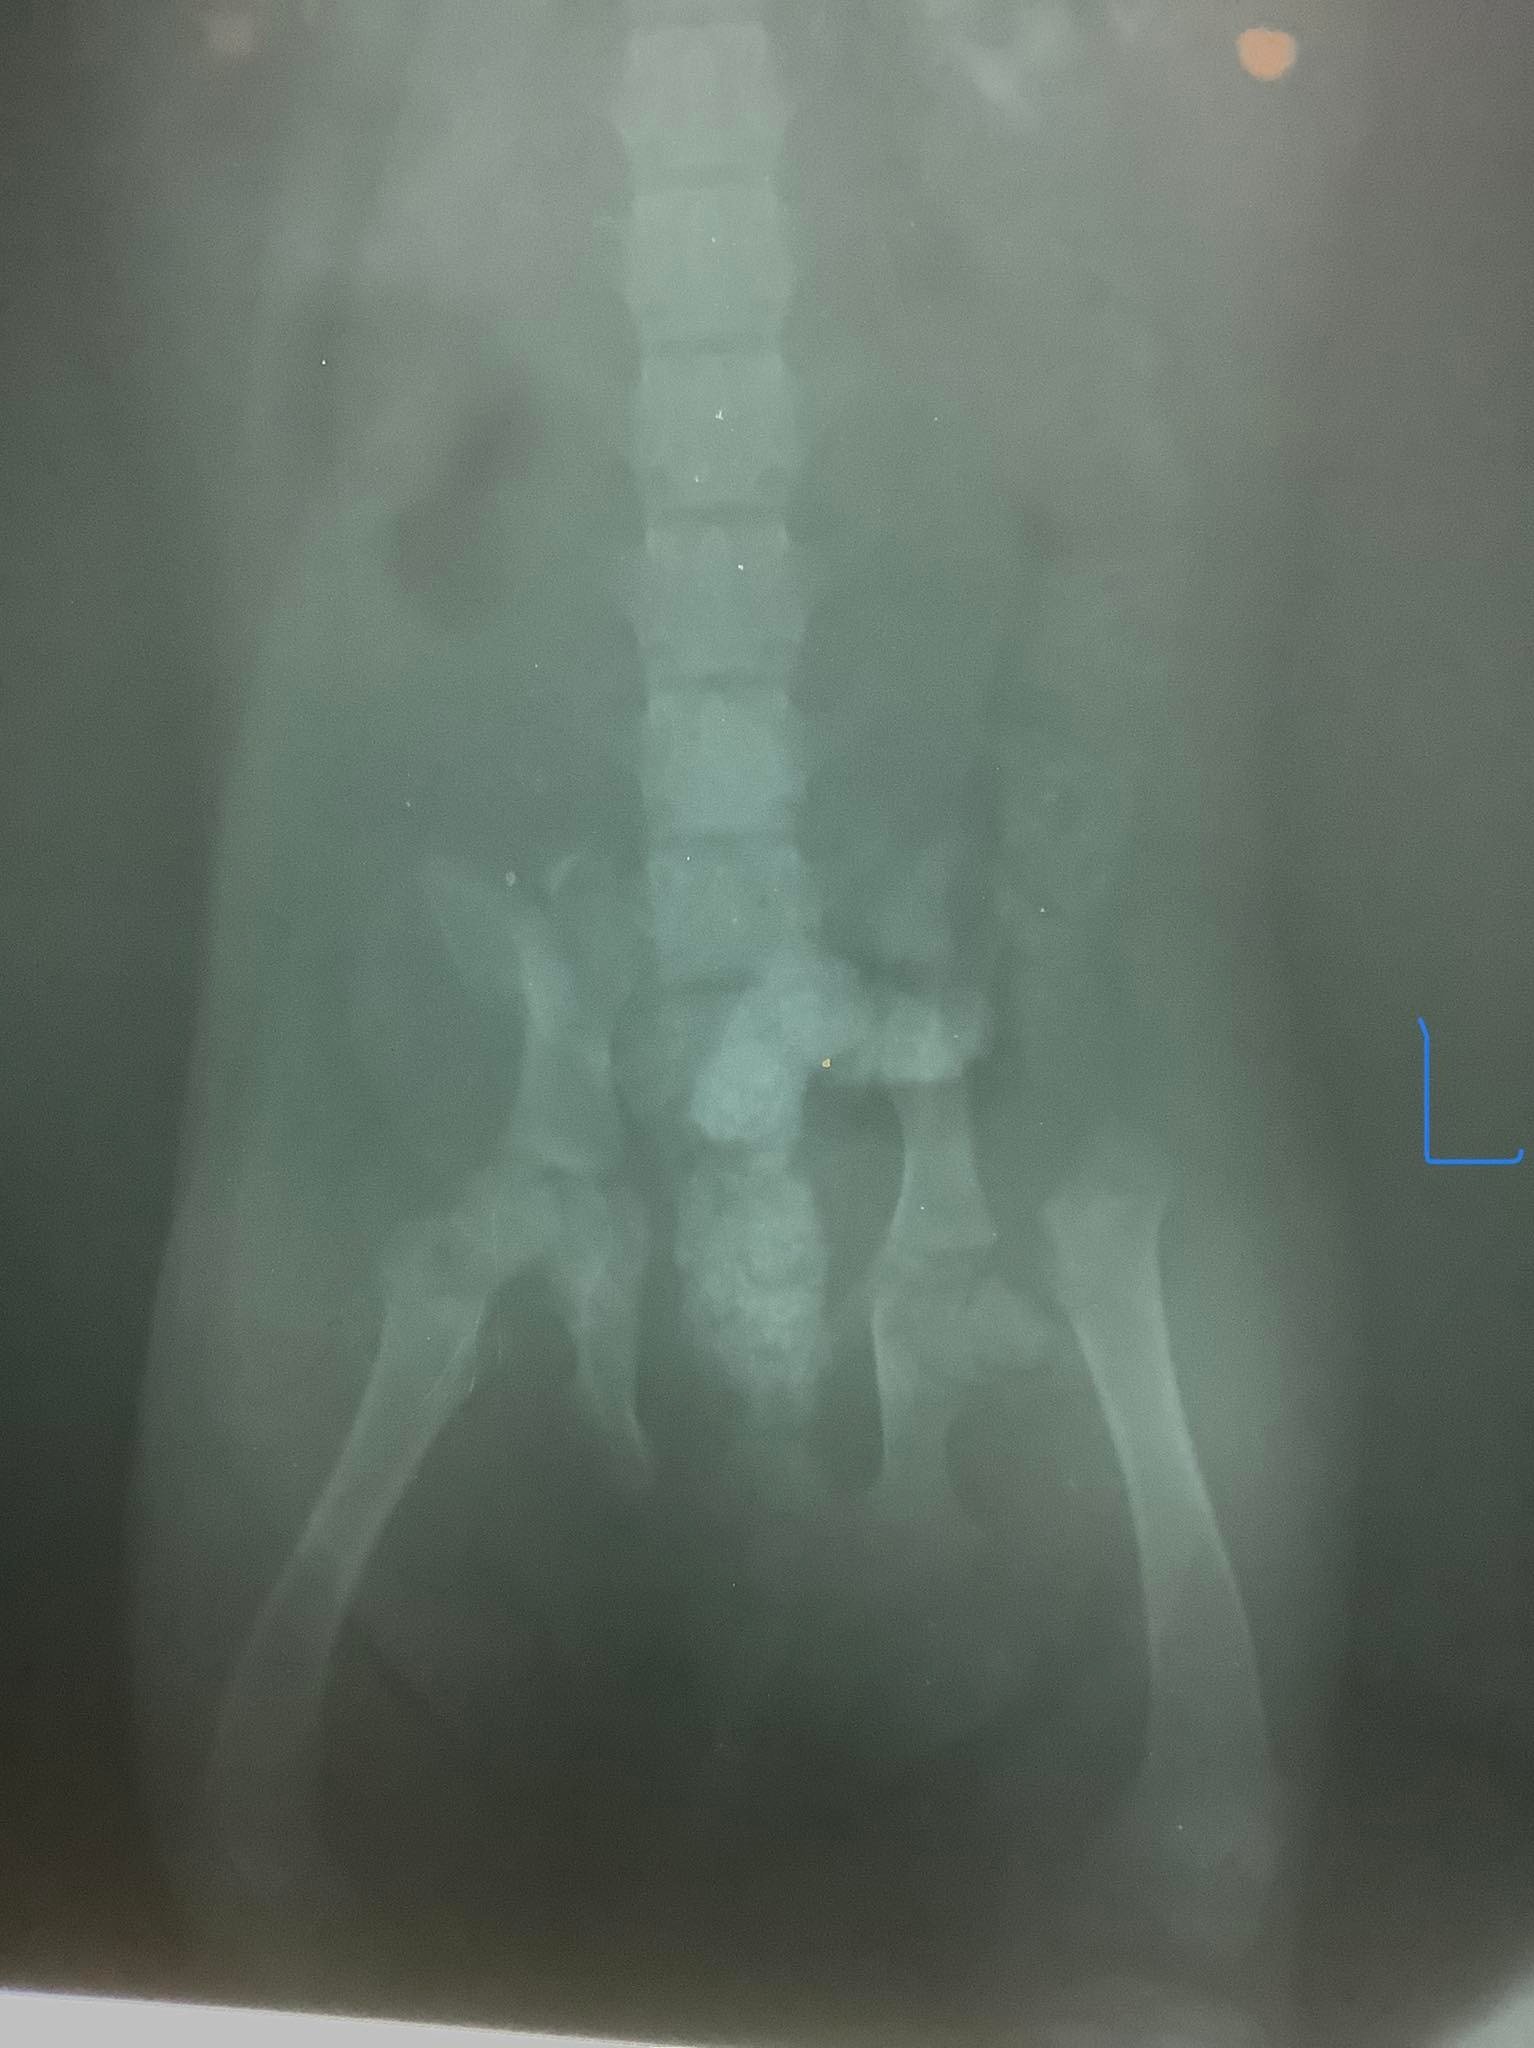

His broken leg will heal in time, provided his movement is restricted for a few months.

Ollie We have some extremely sad and very unexpected news to share. Little Ollie died suddenly today, 17 October 2022. We rescued him at 4 months old after he got hit by a car that left him lying on the side of the road. His leg was fractured too severely to heal so we had Click to see post….